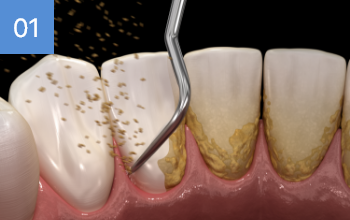

상악의 경우 단순매복으로 발치 및 동시에 하악 잇몸뼈에

깊게 박혀잇는 고난이도 케이스, 잇몸절개 후 치아 분리하여

발치하였으며